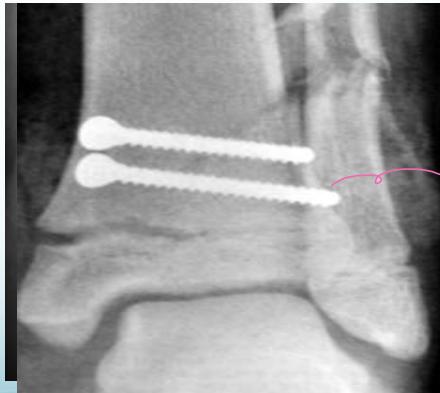

- Unstable: K-wire / screws with cast

Intra-articular (Type III / IV)

- Anatomical reduction and internal fixation

Case Example: 12-year-old male, Salter-Harris Type II